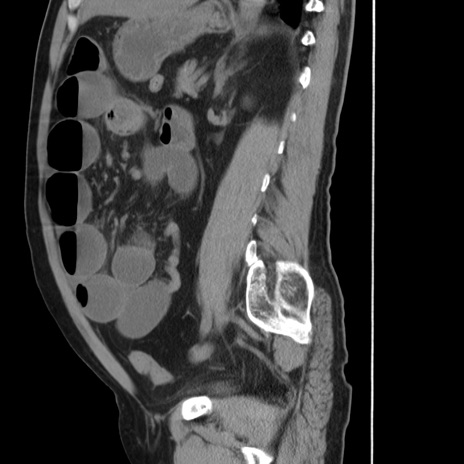

症例20(矢状断像)

【症例】 60歳代男性

【主訴】 腹部膨満、嘔吐

【現病歴】5日前頃より倦怠感を認め食事量減少し4日前の朝嘔吐、食事摂取困難となった。 3日前近医受診し点滴施行され整腸剤などを処方された。 当日他院を受診し、腹部膨満著明、炎症反応の上昇(CRP10.8、WBC11200)あり、紹介受診となる。

【身体所見】 意識JCS1 受け答えがはっきりしないBP 111/57mHg、 P 67bpm、、BT35.2°C、SpO2 97%(RA)、 腹部:膨隆、打診で鼓音あり、全体的に圧痛有り、腸蠕動音(-)、反跳痛ははっきりせず。

【データ】WBC 11400、CRP 14.20